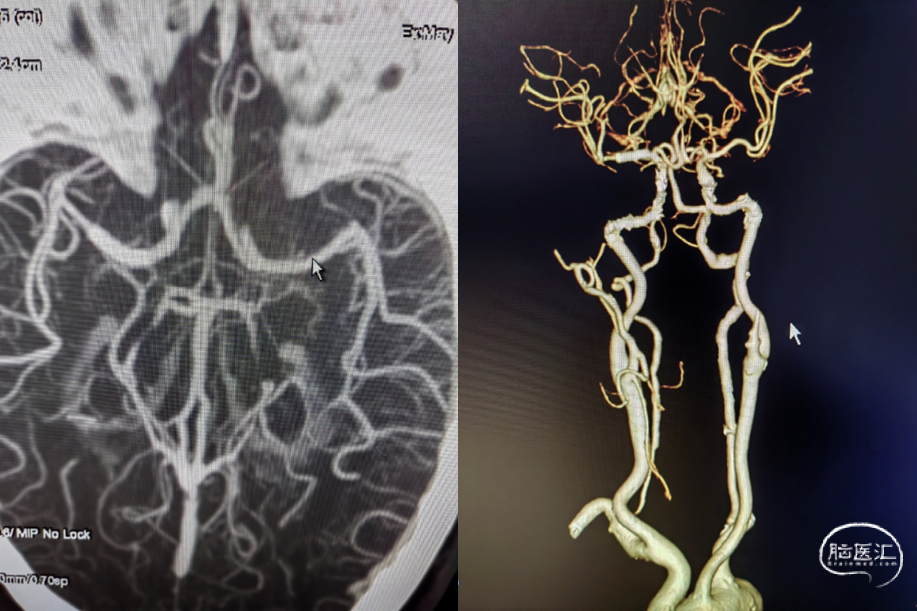

(术后14d CTA)RMCA-M1支架植入术后改变。

重要影像结论:右侧大脑中动脉M1段局限性狭窄。

病变部位:右侧大脑中动脉M1段重度狭窄

远端正常血管直径(mm):2.4

狭窄处最小直径(mm):0.6

病变长度(mm):12

狭窄度(%):80%